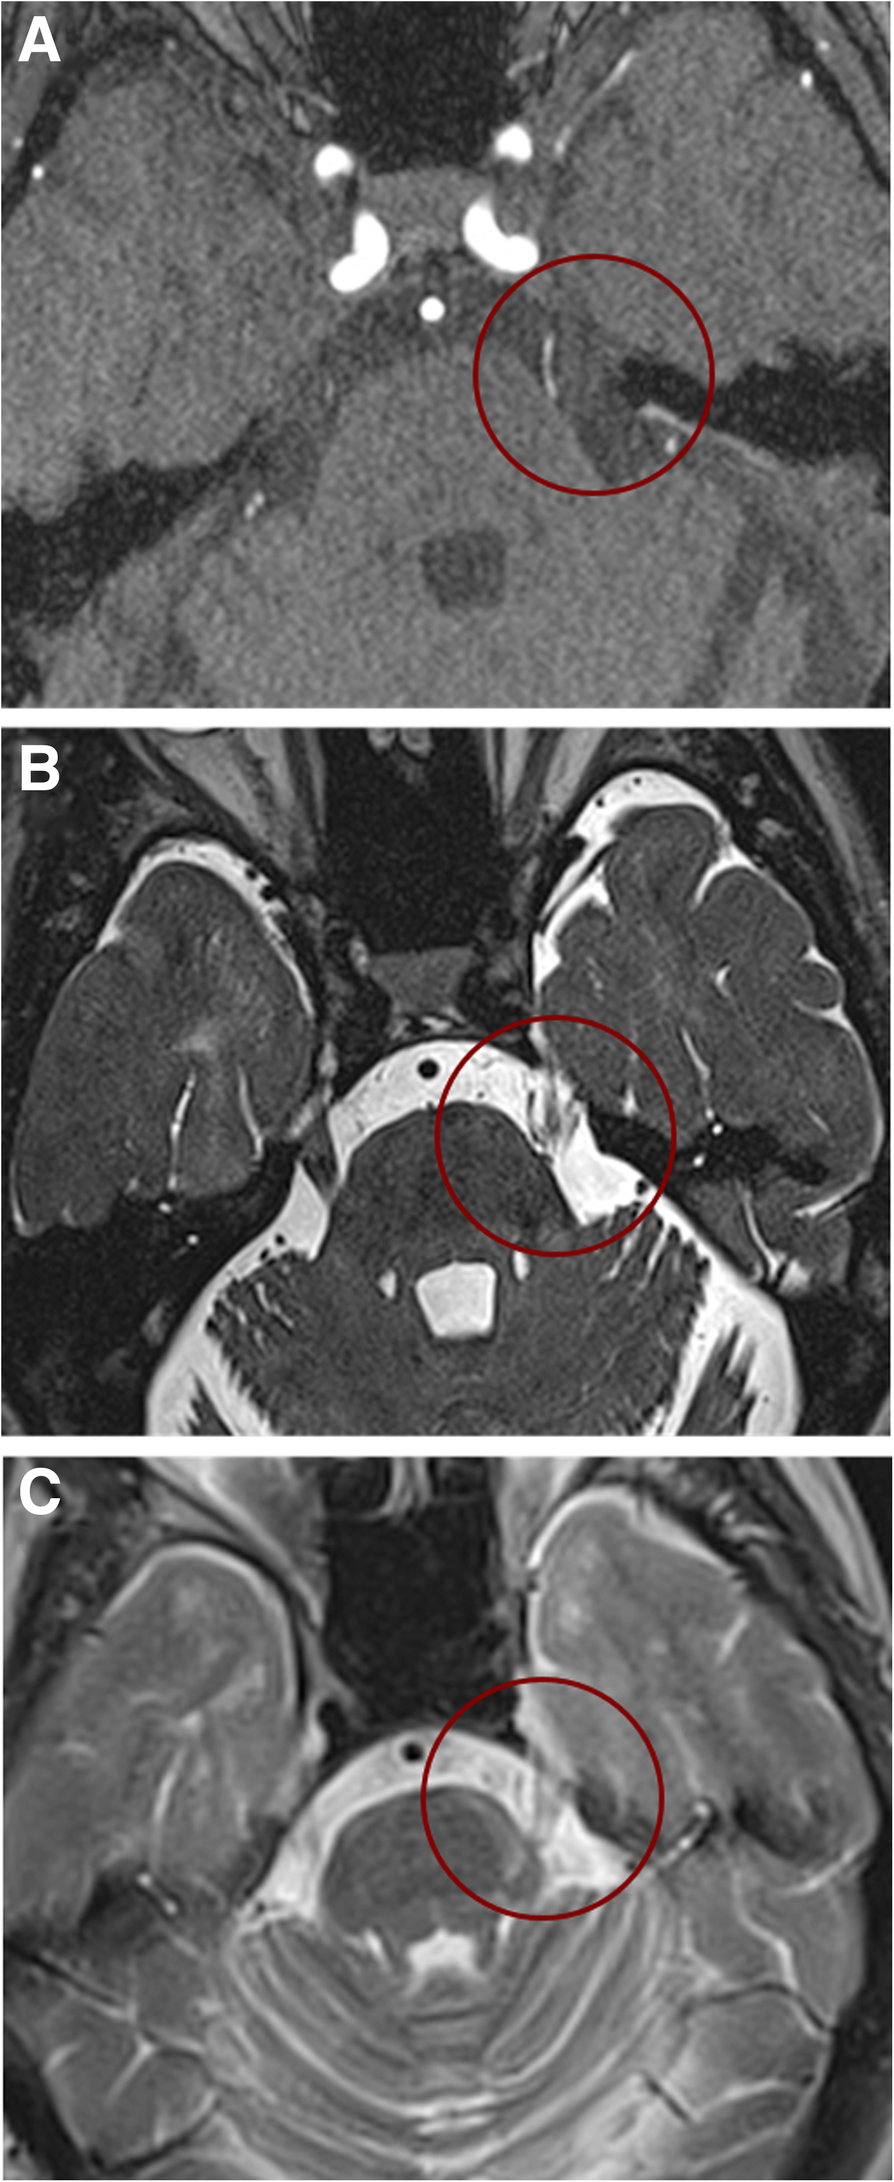

Trigeminal Nucleus Mri

Trigeminal Nucleus Mri CT Guided Gasserion Ganglion Block - Precise Saviour